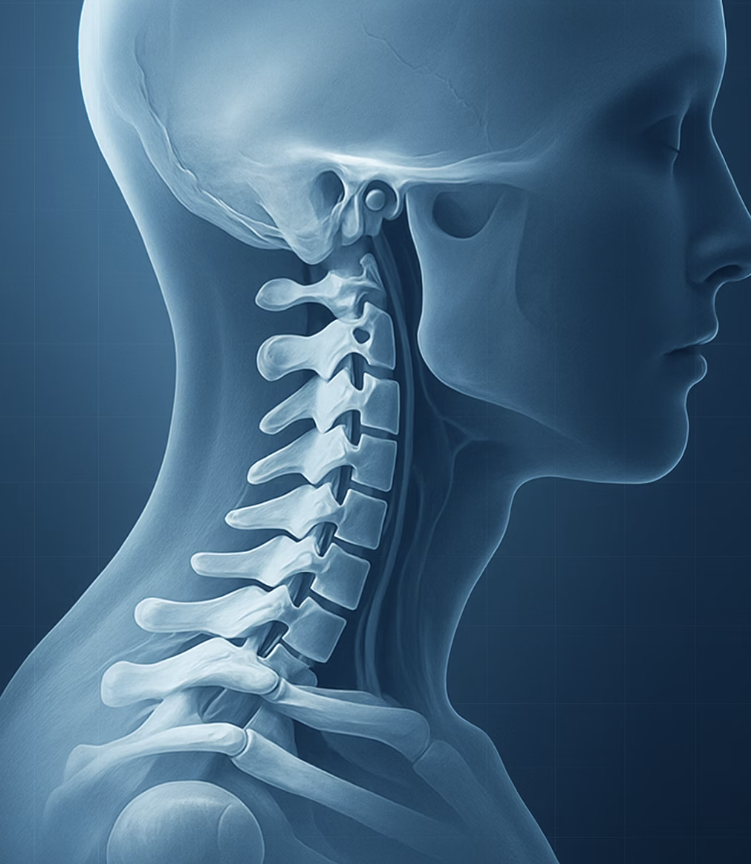

반면, '경추성 두통'은 이름 그대로 그 원인이 머리가 아닌 '목(경추)'에 있습니다. 잘못된 자세나 퇴행성 변화로 인해 목뼈나 주변 근육, 인대가 손상되면서, 그 통증이 신경을 타고 머리로 뻗쳐나가는 '구조적인' 문제입니다. 마치 벽 속의 전선이 잘못되어 엉뚱한 곳의 전등이 깜빡이는 것과 같죠.

하지만 '경추성 두통'은 이러한 소화기 증상이나 감각 예민 증상은 거의 없습니다. 대신, 두통이 시작될 때 거의 항상 '목과 어깨의 뻣뻣함'이나 '통증'을 동반합니다. 손으로 목 뒤나 어깨를 눌렀을 때 유독 아픈 지점이 있거나, 고개를 돌릴 때 움직임이 부자연스럽고 아프다면, 그 두통의 범인은 목에 있을 확률이 매우 높습니다.

반면, '경추성 두통'의 통증은 울리는 느낌보다는 '뻐근'하거나 '묵직'하게 조여오는 느낌에 가깝습니다. 통증은 주로 뒷목이나 뒤통수에서 시작되어 정수리나 이마, 눈 주변으로 뻗쳐나가는 양상을 보입니다. 움직인다고 해서 통증이 급격히 심해지기보다는, 꾸준히 지속되는 둔한 통증인 경우가 많습니다.